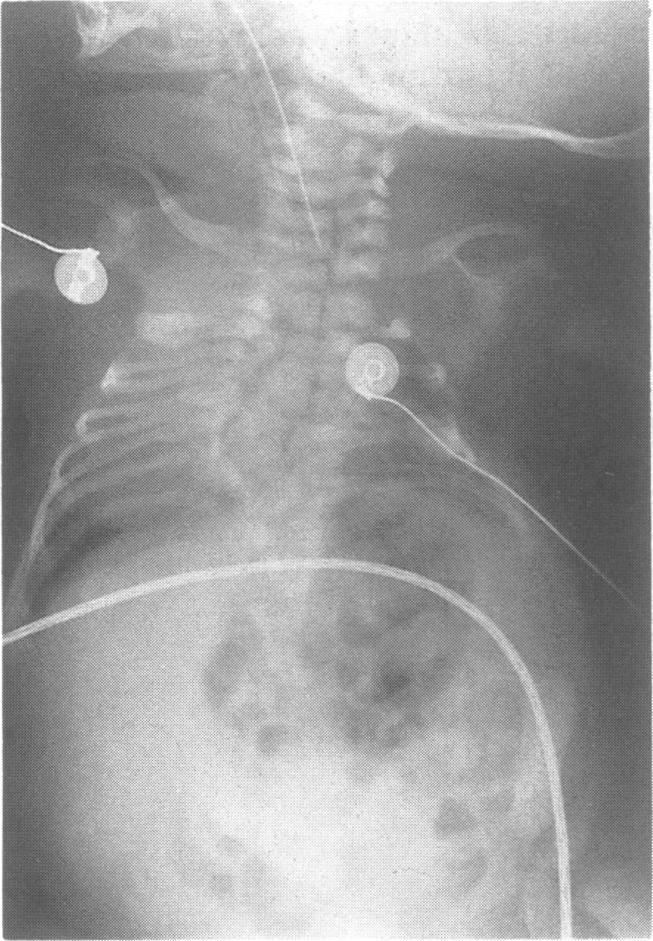

Spondylocostal dysplasia (Jarcho-Levin syndrome) comprises multiple malformations of the vertebrae and ribs coupled with a characteristic clinical picture of short neck, scoliosis, short trunk, and deformity of the rib cage. We describe a patient with the syndrome who also had spina bifida and diastematomyelia. We surmise that this association is not coincidental. Additional evidence is needed to support the hypothesis that spondylocostal dysplasia and neural tube defects are aetiologically related.

脊椎肋骨发育不良(雅尔乔-莱文综合征)包括脊椎和肋骨的多种畸形,并伴有短颈、脊柱侧弯、躯干短小和胸廓畸形的特征性临床表现。我们描述了一名患有该综合征且还患有脊柱裂和脊髓纵裂的患者。我们推测这种关联并非偶然。需要更多证据来支持脊椎肋骨发育不良与神经管缺陷在病因学上相关的假说。